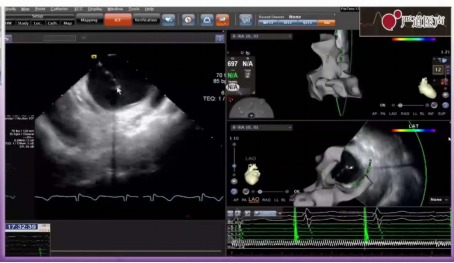

手术由李嘉教授完成,患者为71岁男性,诊断为快慢综合征、阵发性房颤、病窦。本例患者先给予导管消融,根据情况给予起搏器治疗。采用双房间隔穿刺及鞘中鞘策略,减少消融难度,但是要注意排气。通过超声指导下的T3D法实现零射线房间隔穿刺,房间隔穿刺第1针(鞘中鞘)在最舒适位置,第2针穿刺在稍靠上位置。在穿刺过程中会出现跳跃现象,穿刺后送入鞘管,退针,注射肝素6000U。固定内鞘,外鞘内送2cm,退出外鞘,鞘管顺利进入,换鞘成功,随后进行第2针穿刺。患者消融过程顺利,消融效果良好。

鞘中鞘示意图

房间隔穿刺示意图

穿刺位点示意图